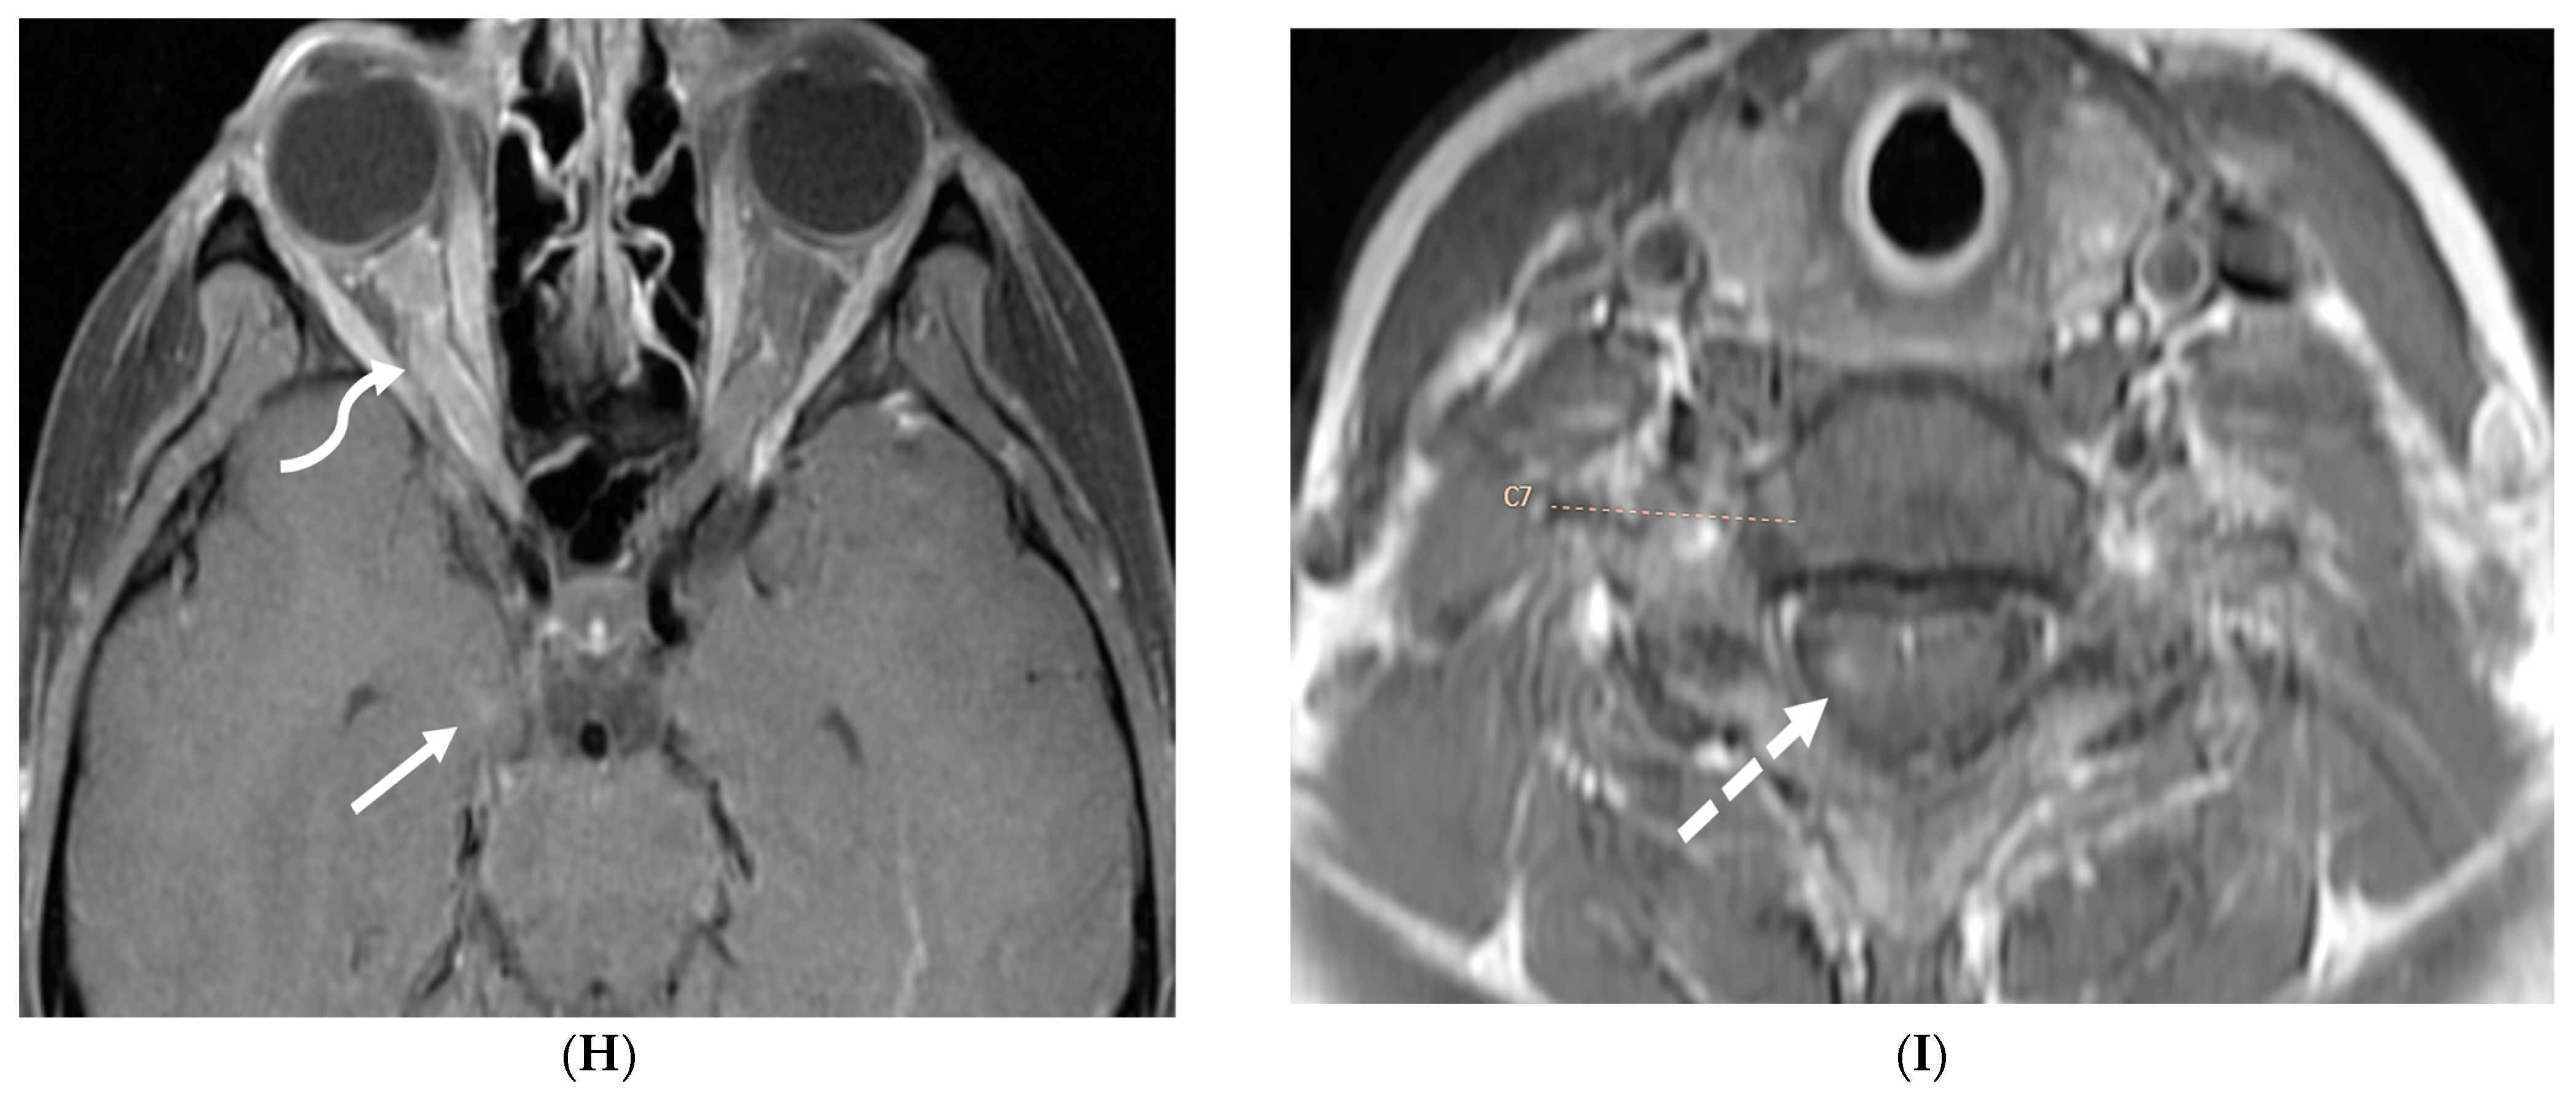

Figure 15.

Axial DWI (A), axial ADC (B), axial T1 FS post contrast (C) and Fluorodeoxyglucose Positron Emission Tomography (FDG–PET) scan (D): 13-year-old male with bilateral leg pains, headache, fever and weight loss: Blood tests and CT scan were concerning for Burkitt’s lymphoma. There is heterogeneous calvarial bone marrow signal with restricted diffusion (arrows) and patchy enhancement (curved arrows). Diffuse thickening and enhancement of pachymeninges in the supratentorial compartment is noted (dashed arrows). Findings are most consistent with lymphomatous involvement. Multifocal diffuse/heterogeneous pattern of FDG uptake within the axial and appendicular skeleton and the calvarium (open arrows). Intense FDG avid uptake is seen in the presacral mass (star).

Figure 16.

16-year-old female with 4 months history of globus sensation and recent botox injection of lower esophageal junction. Headache and vomiting for past week: Esophagogram (A), Axial T2 orbits (B), axial FLAIR (C) and post contrast T1 (D,E): Narrowing of the Gastroesophageal (GE) junction with beaked configuration and mild distention of the lower esophagus likely from early achalasia (black arrow). There is bilateral papilledema indicating raised ICP (dashed arrows) and sulcal hyperintensity (curved black arrows). Diffuse LME in the supra-and-infratentorial regions and along optic sheaths raising the concern for leptomeningeal carcinomatosis (white arrows). Pathology: Gastric adenocarcinoma metastasis.

Figure 17.

Axial T2 FS (A), axial Susceptibility weighted imaging (SWI) (B), axial DWI (C), post contrast sagittal and axial T1 post contrast (D,E): 19-year-old female with history of stage IV neuroblastoma, left paraspinal primary ganglioneuroblastoma, treated with chemotherapy, radiation and bone marrow transplant presents with headache. There are extensive hemorrhagic leptomeningeal masses, both supra and infratentorial region (arrows). The lesions also demonstrate restricted diffusion which could be secondary to internal hemorrhage or high cellularity of the tumor(curved arrows). The larger masses invade the cortex of both cerebral hemispheres, with surrounding vasogenic edema (black arrow). Avid enhancement of the lesions is seen along with overlying dura (dashed arrows). Features are in keeping with extensive leptomeningeal metastatic neuroblastoma.